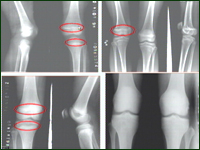

主持人:骨延长手术具体是怎么进行的? 张志刚:来看一张电脑图示,骨延长手术是将长骨截断,安装上延长器械,按照一定的速度把它牵开,让骨头慢慢地生长成型。正常的骨头是通过骨头两端的骨骺长出来的,来看一组X光片,红圈部分就是骨骺,正常人的骨骺内充满软骨,随着软骨的不断生长和骨化,骨头就长长了,一旦骨骺闭合,骨头就不会再长长了,如果小孩由于某种原因造成了一侧骨骺过早闭合如感染、外伤等,那么这一侧骨头的生长就受到了限制,由于对侧肢体还在继续生长,就出现了肢体不等长的情况。